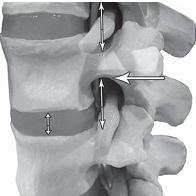

На фото № 6 макета позвоночника наблюдается смещение (подвывих) суставных поверхностей дугоотростчатых суставов. На фото № 7 наблюдается смещение (подвывих) суставных поверхностей дугоотростчатого сустава (увеличенный вариант). ![]() На фото № 8 макета позвоночника наблюдается перерастяжение дугоотростчатых суставов вследствие вытяжения. На фото № 9 наблюдается перерастяжение дугоотростчатого сустава (увеличенный вариант). ![]() Фото № 10 На фото № 10 макета позвоночника наблюдается нормальное взаимоотношение суставных поверхностей дугоотростчатых суставов, в норме высота межпозвонкового диска и межпозвонковых отверстий. ![]() Фото № 11 На фото № 11 макета позвоночника наблюдается смещение (подвывих) суставных поверхностей дугоотростчатых суставов. Подобное смещение, как правило, происходит вследствие развития дегенеративно-дистрофических процессов в межпозвонковом диске. При этом уменьшается высота диска, сужается просвет фораминального отверстия (межпозвонкового), что может способствовать ущемлению спинномозговых корешков (нервов) и сосудов. ![]() Фото № 12 На фото № 12 макета позвоночника наблюдается перерастяжение дугоотростчатого сустава вследствие вытяжения, расширение фораминального отверстия, а также растяжение задних отделов фиброзного кольца межпозвонкового диска и сближение вентральных (передних) отделов тел позвонков. Это приводит межпозвонковый диск в клиновидное состояние, что способствует выталкиванию содержимого межпозвонкового диска из передних его отделов в задние. |